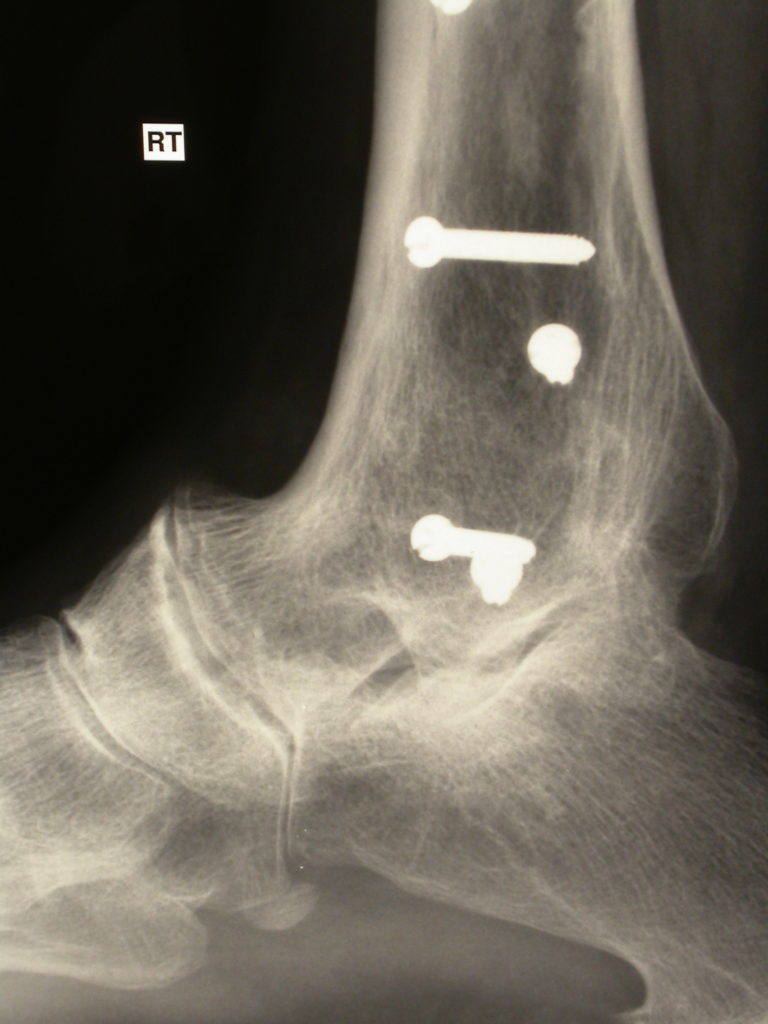

loose ankle replacement2 Dr Gerald Yeo Queensland trained and What Are Ankle Replacements Made Of The muscles and soft tissue (any other tissue other than bone) in the region are moved to allow access to the. An incision is made in the front part of your ankle and lower leg. It’s also called ankle arthroplasty. Ankle replacement surgery involves replacing damaged bone and cartilage in the ankle joint with an artificial joint, called a prosthesis.. What Are Ankle Replacements Made Of.